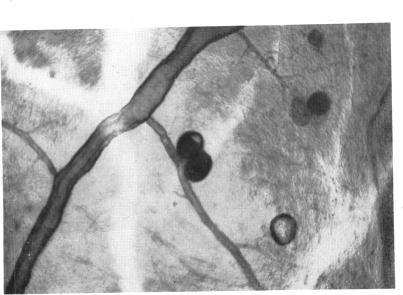

Vascular changes in diabetes with particular reference to the retinal vessels; preliminary report.

Br J Ophthalmol. 1949 Jul;33(7):407-20. doi: 10.1136/bjo.33.7.407.